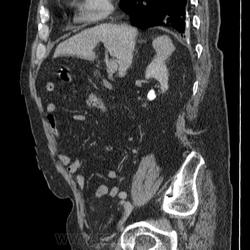

КТ ОБП+С Объемное гиперваскулярное образование почки. Почечно-клеточный рак.

Мужчина 82 года. Отец коллеги с другого отделения. На УЗИ киста почки. Решили сделать КТ. Жалобы на боль в поясничном отделе позвоночника (неудивительно из-за жуткого остеохондроза и м/п грыж). Макрогематурию отрицает. Микрогематурии не выявлено по ОАМ, лишь протеинурия. Кисты подтвердились ну и черт с ними  хуже то, что в верхнем сегменте правой почки похоже ПКР, характеристика контрастирования соответсвует, тем более еще свеж в памяти предыдущий случай. Смущают надпочечники, не "стрельнул" ли в правый mts? А в опухоли гиподенсивный учаток в артериальную фазу - участок некроза, кровоизлияния?

Почечно-клеточный рак, гистологически - светлоклеточный, степень дифференцировки не помню.

Образование в верхнем полюсе правой почки: гиперденсивное в артериальную фазу, гиподенсовное в венозную и отроченную = почечно-клеточный рак